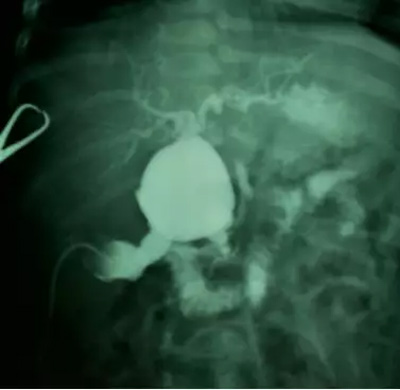

2.小儿外科创造性地利用术前MR 胆道三维重建与术中胆道造影相结合的方法,精准地判断胆总管囊肿的类型、胆总管末端与胰管的关系、肝管是否狭窄,从而在术中能精确地剥离胆总管、处理肝管狭窄。

患儿因“腹痛、皮肤黄染3天”以“胆总管囊肿、胆道梗阻并感染”入院。行腹部MR检查发现胆总管呈囊状扩张,入院后在B超引导下行胆管穿刺引流术,出院后恢复1个月后再次入院。经引流管行逆行胆道造影,显示胆总管呈囊状扩张,胆总管、胰管合流异常。